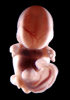

Carnegie Stage 18 (44 post-ovulatory days)

Most embryos at stage 18 are approximately 44 postovulatory days old and measure 13-17 mm in length. Distinguishing criteria for this stage include cervical and lumbar flexures, distinct notching in the hand plate, the first appearance of the elbow, eyelid folds may appear in more advanced specimens, and auricular hillocks begin to form distinct parts of the external ear.